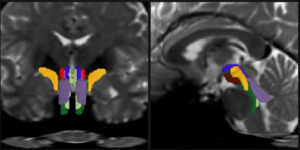

Opening a new window on the brainstem, a new tool reliably and finely resolves distinct nerve bundles in live diffusion MRI scans, revealing signs of injury or disease.